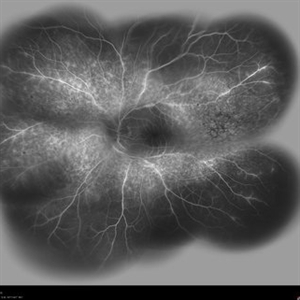

Behcet's Disease Behcet's DiseaseMar 13 2013 by Hamid Ahmadieh, MD Early phase FA of the left eye of a 23-year-old man with retinal vasculitis due to Behcet's disease . Photographer: Solmaz Shahmohammad, Negah Eye Center, Tehran Imaging device: Heidelberg Spectralis Condition/keywords: retinal vasculitis

Behcet's Disease Behcet's DiseaseMar 13 2013 by Hamid Ahmadieh, MD Mid phase FA of the left eye of a 23-year-old man with retinal vasculitis due to Behcet's disease . Photographer: Solmaz Shahmohammad , Negah Eye Center, Tehran Imaging device: Heidelberg Spectralis Condition/keywords: retinal vasculitis

Behcet's Disease Behcet's DiseaseMar 13 2013 by Hamid Ahmadieh, MD Late phase FA of the left eye of a 23-year-old man with retinal vasculitis due to Behcet's disease . Photographer: Solmaz Shahmohammad, Negah Eye Center, Tehran Imaging device: Heidelberg Spectralis Condition/keywords: retinal vasculitis

Behcet's Disease Behcet's DiseaseMar 13 2013 by Hamid Ahmadieh, MD Wide field FA of the left eye of a 23-year-old man with retinal vasculitis due to Behcet's disease . Photographer: Solmaz Shahmohammadi , Negah Eye Center, Tehran Imaging device: Heidelberg Spectralis Condition/keywords: retinal vasculitis